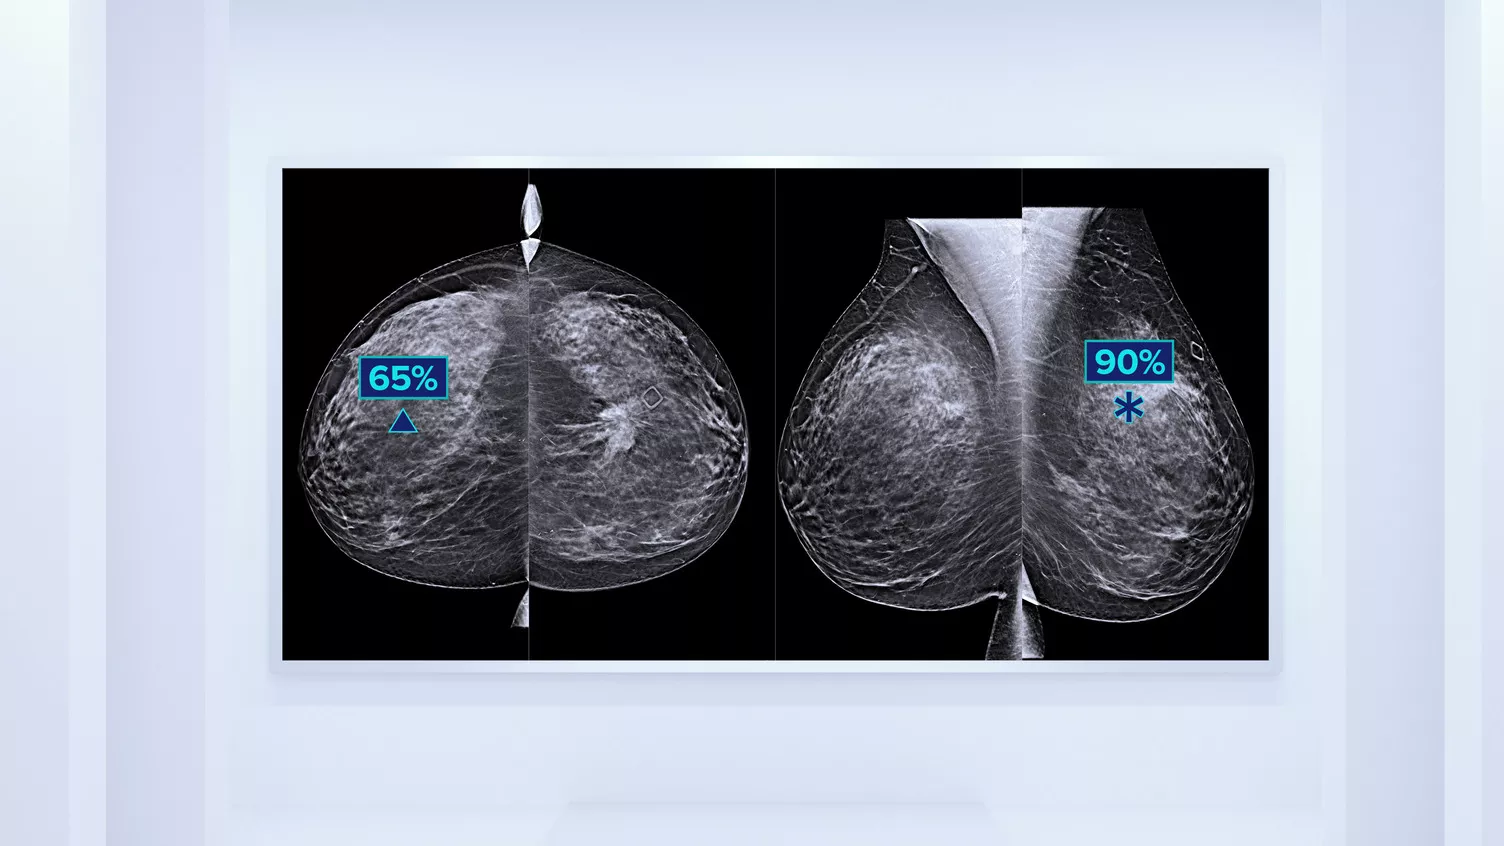

Sabemos que una densidad mamaria alta aumenta el riesgo de cáncer de mama en mujeres.1 Por tanto, es fundamental realizar un análisis preciso y sin sesgo. El software de la tecnología Quantra, basado en aprendizaje automático, analiza las imágenes 2D™ y de tomosíntesis para determinar la distribución y la textura del tejido parenquimatoso. Clasifica las mamas en cuatro categorías de composición mamaria de acuerdo con las directrices del Atlas BI-RADS (5.ª edición) del American College of Radiology (ACR).2

Además del volumen, el patrón y la textura del tejido fibroglandular pueden ser igualmente decisivos para la predicción mamográfica del riesgo de cáncer.3-5 ​​Mediante el análisis y la clasificación de la textura y el patrón de la mama, nuestra tecnología puede ofrecer la información precisa que necesita para realizar una clasificación más fiable y completa y, de este modo, diseñar con seguridad una vía de detección específica para cada paciente.

El algoritmo de aprendizaje automático objetivo asigna una categoría de densidad de mama de acuerdo con los patrones y la textura del tejido de la mama.

* Las clasificaciones se basan en las categorías BI-RADS del ACR, de acuerdo con las directrices revisadas publicadas en el Atlas BI-RADS (5.ª edición) del American College of Radiation (ACR). Estas directrices tienen en cuenta el patrón y la textura, y no solo el volumen, a la hora de determinar la densidad.